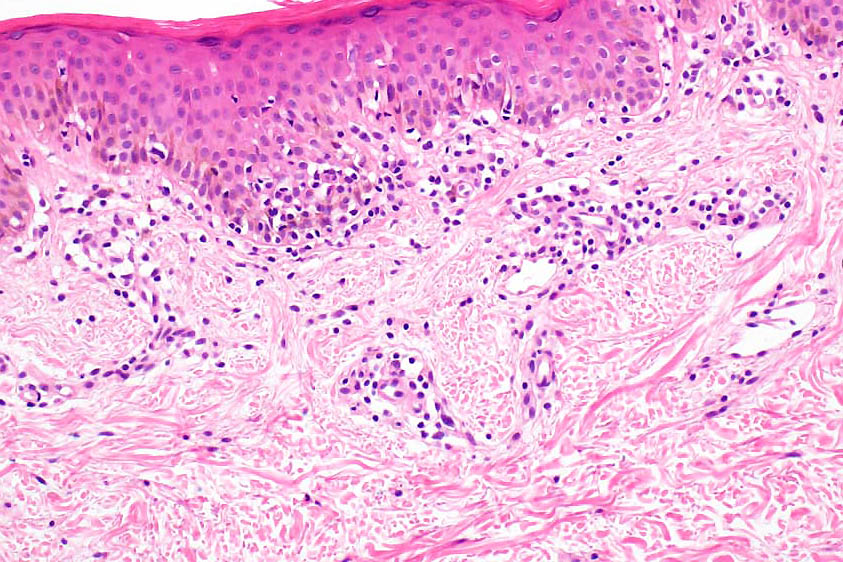

Histological features

•Indistinguishable from classical mycosis fungoides with the additional feature of marked pigmentary incontinence

•CD8+ve cells may predominate

•Hypopigmentation likely associated with melanocytic toxicity & reduced melanocyte population although this isn’t always a feature

•Masson-Fontana may show reduced melanin with SOX10 & with Melan-A showing reduced numbers of melanocytes